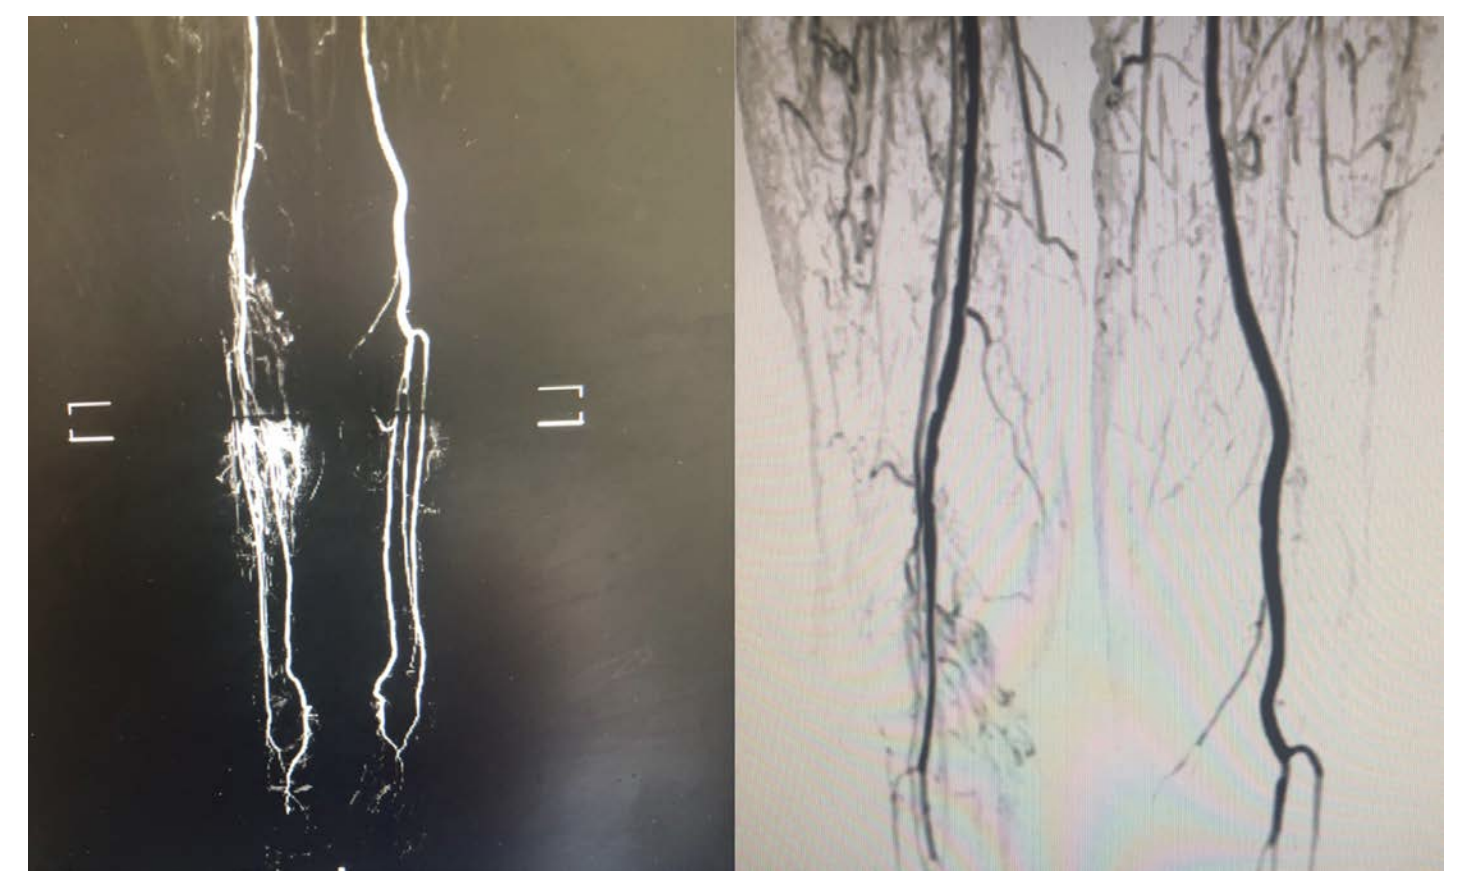

A 76-year-old woman with a history of hyperlipidemia and hypothyroidism developed new onset left calf claudication immediately after a 13-hour flight from Houston to Rome. The patient did not have any prior history of peripheral artery disease, hypertension, coronary artery disease, Marfan’s syndrome, fibromuscular dysplasia, ongoing smoking, atrial fibrillation, cardiomyopathy, clotting disorder, or knee trauma/surgery. Four weeks after the onset of the symptoms, she reported numbness, coolness in the left foot, and nightly left toes resting pain. Physical examination was notable for absent pulse of the left popliteal, posterior tibials, and dorsalis pedis arteries. The left lower extremity motor and sensory functions were grossly preserved and left foot coolness was apparent. An arterial Doppler ultrasound of the left lower extremity depicted monophasic flow in the distal popliteal and tibio-pedal vessels. An urgent left lower extremity magnetic resonance angiography (MRA) demonstrated segmental atherosclerotic disease with mild to moderate stenosis of the left superficial femoral artery and proximal popliteal artery, distal popliteal artery severe attenuation, and extensive collateral formation that originated proximal to the attenuated segment and ended in the infra-popliteal vessels. In the axial plane, a dissection flap was apparent (Figures 1-2).